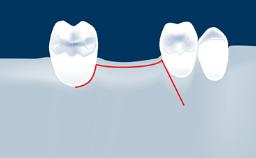

In this short microlearning module on digitally guided sinus floor elevation, we delve into a specialized aspect of the digital workflow for implant-guided surgery, focusing on the use of digital guides in the sinus floor elevation technique.

• describe the indications for digital guides in SFE